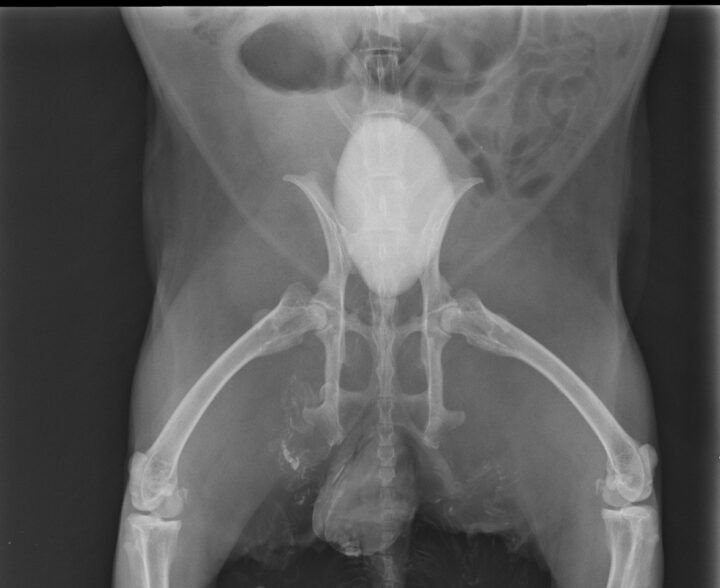

Diagnosis is typically based on clinical signs, physical examination, urinalysis and imaging. The urine may appear cloudy or contain visible sediment. Radiographs can help assess the amount of sludge present and rule out other issues such as urolithiasis (Figure 2). Urinary ultrasound is another useful tool, providing a more detailed view of the bladder wall and sludge accumulation.

The clinical signs of urolithiasis in rabbits include haematuria, dysuria, frequent urination and stranguria. In some cases, the stones can cause a complete obstruction of the urinary tract, which is a medical emergency (Circella et al., 2021). Diagnosis is confirmed through radiographs, where the stones will appear as radiopaque structures, or via ultrasound, where uroliths result in acoustic shadowing.

Common symptoms of urolithiasis in guinea pigs include stranguria, haematuria and signs of discomfort or pain when urinating, such as vocalisation. Diagnosis of urolithiasis in guinea pigs is similar to diagnosis in rabbits, using physical examination, urinalysis and imaging techniques, such as radiographs or ultrasound. Radiographs will often reveal the presence of stones (Figure 4), though small stones may be missed if they are not radiopaque. Ultrasound can be particularly useful for detecting smaller stones or those located in the kidneys or ureters.